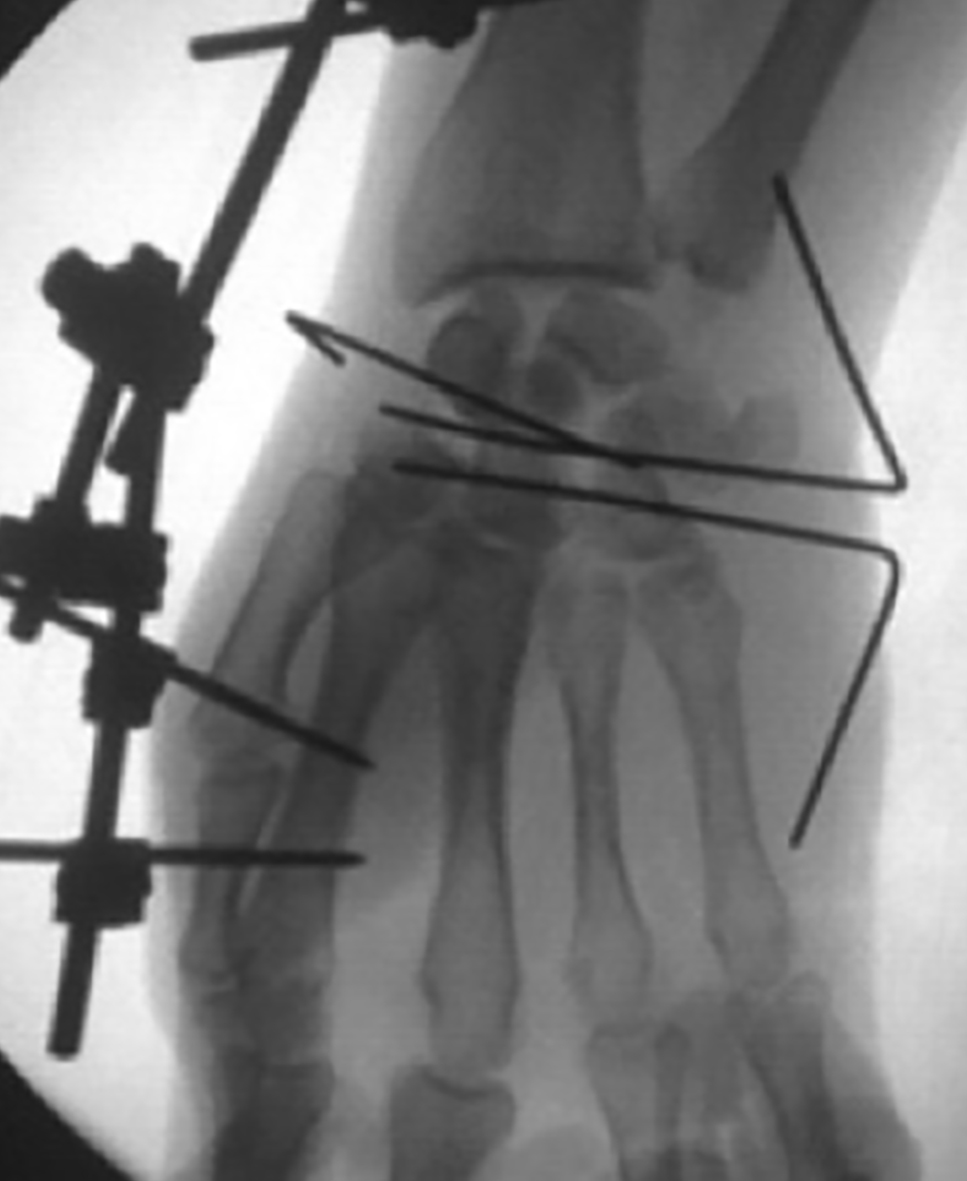

Paciente de sexo masculino, de 26 años, diestro, sin antecedentes personales a destacar, que fue embestido por automóvil mientras manejaba su moto. El paciente presentó una lesión encefálica focal que requirió tratamiento médico. Estuvo en coma 20 días, aparentemente sin otras lesiones. Luego, ya con vida de relación retomada, el paciente relató dolor e impotencia funcional de su mano derecha. Tumefacción y dolor a la movilización (pasiva-activa) y a la prehensión en el examen físico. Las radiografías y el TC mostraron una luxación volar de hueso grande de mano derecha (Figura 1) asociada a fracturas de la base del tercer metacarpiano y de hueso piramidal, ambas sin desplazamiento (Figura 2). A las 8 horas de establecer el diagnóstico se realizó una reducción abierta por vía palmar con fijación interna, con alambres de Kirchner de 1,5 mm, (Figura 3). Se agregó un mini fijador externo para proteger la estabilidad de la osteosíntesis del carpo y manejar las partes blandas lesionadas. No se realizó reconstrucción ligamentaria.